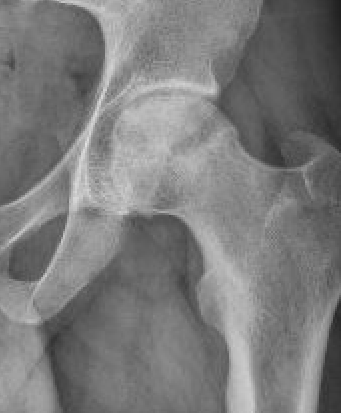

Osteotomy

Theory

Move the avascular segment away from weight-bearing area

- must have sufficient intact femoral head to bear weight upon

Indications

Young patient

Stage III / no osteoarthritis

Small lesion: CNA <200°

Not on steroids

Technique

CT / MRI decide osteotomy direction

- typically anterolateral AVN

- undergoes a varus flexion intertrochanteric osteotomy